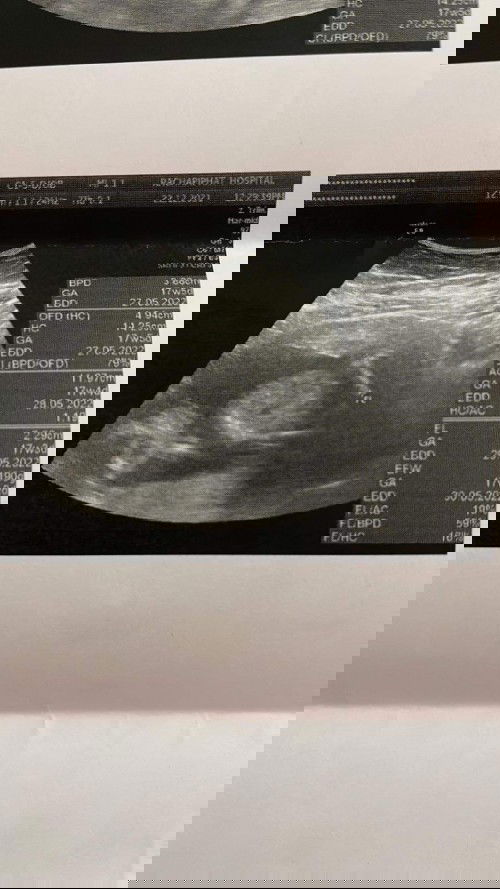

แบบนี้มีใครพอจะดูออกมั้งไหมคะ ว่าหญิงหรือชาย😁😁 ซาวตอน17สัปดาห์ คะ#ขอบคุณสำหรับคำตอบนะคะ คุณหมอไม่ได้บอกเลยคะว่าหญิงหรือชาย